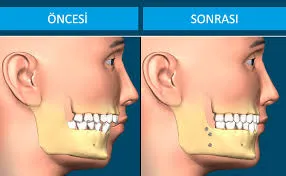

Ortognatik Cerrahi: Çene Bozukluklarının Estetik ve Fonksiyonel Çözümü

Çene Cerrahisi